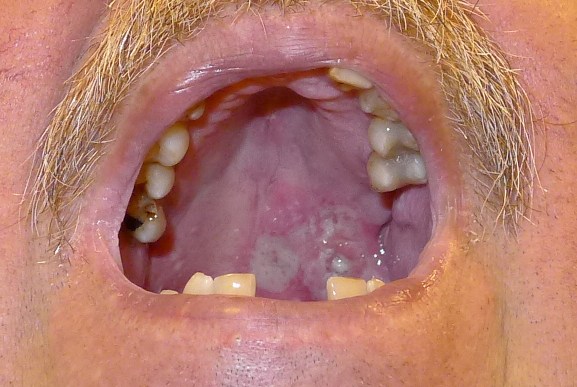

84-jährige demente pflegebedürftige Frau, die ein Geschwür rechts neben der Zunge bemerkt hat.

Erst der Zahnarzt äußerte Malignomverdacht. Plattenepithelkarzinom der Wangenschleimhaut cT2 cNo Mo.![]() |